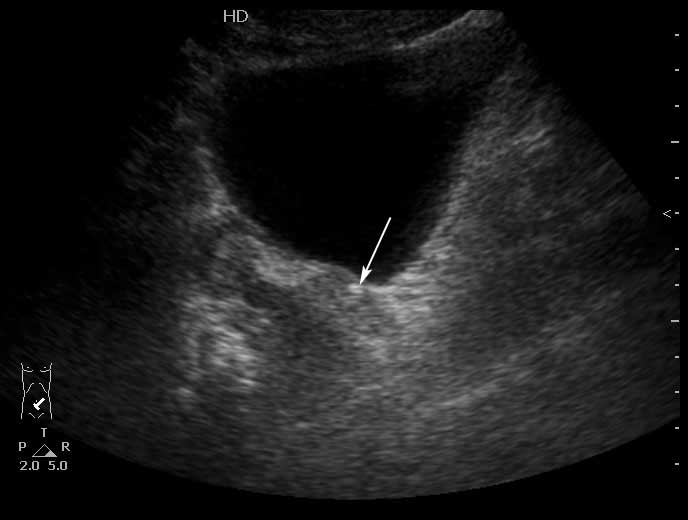

Конкремент в юкставезикальном отделе мочеточника. Пиелонефрит . Субкапсулярный выпот.

Да, МКБ,конкремент юкставезикального отдела мочетоника.

Выпот находится не под капсулой почки, а в периренальном пространстве в самой нижней точке человека прямоходящего.

Особенность этого случая заключается в том,что достаточно выраженные боли не сопровождались расширением ЧЛС, поэтому формула "отсутствие расширения ЧЛС на высоте болей практически исключает уретеролитиаз" здесь оказалась нерабочей.

Проводить инспекцию мочеточника пришлось из-за изменений почки - выпота и повышения эхогенности патенхимы. Как вариант рассматривался тромбоз ПА, но доплерографически он был исключен.

Не видите камня в юкставезикальном отделе мочеточника, предполагаете что это не камень и не в мочеточнике, считаете что это другая патология почки, - что смущает? )

Конкремент в юкставезикальном отделе мочеточника - стрелка.Брехт писал(а):Вокруг камни есть и отёчные стенки мочеточника?; или я допридумываю

Стенки мочеточника без существенных изменений.